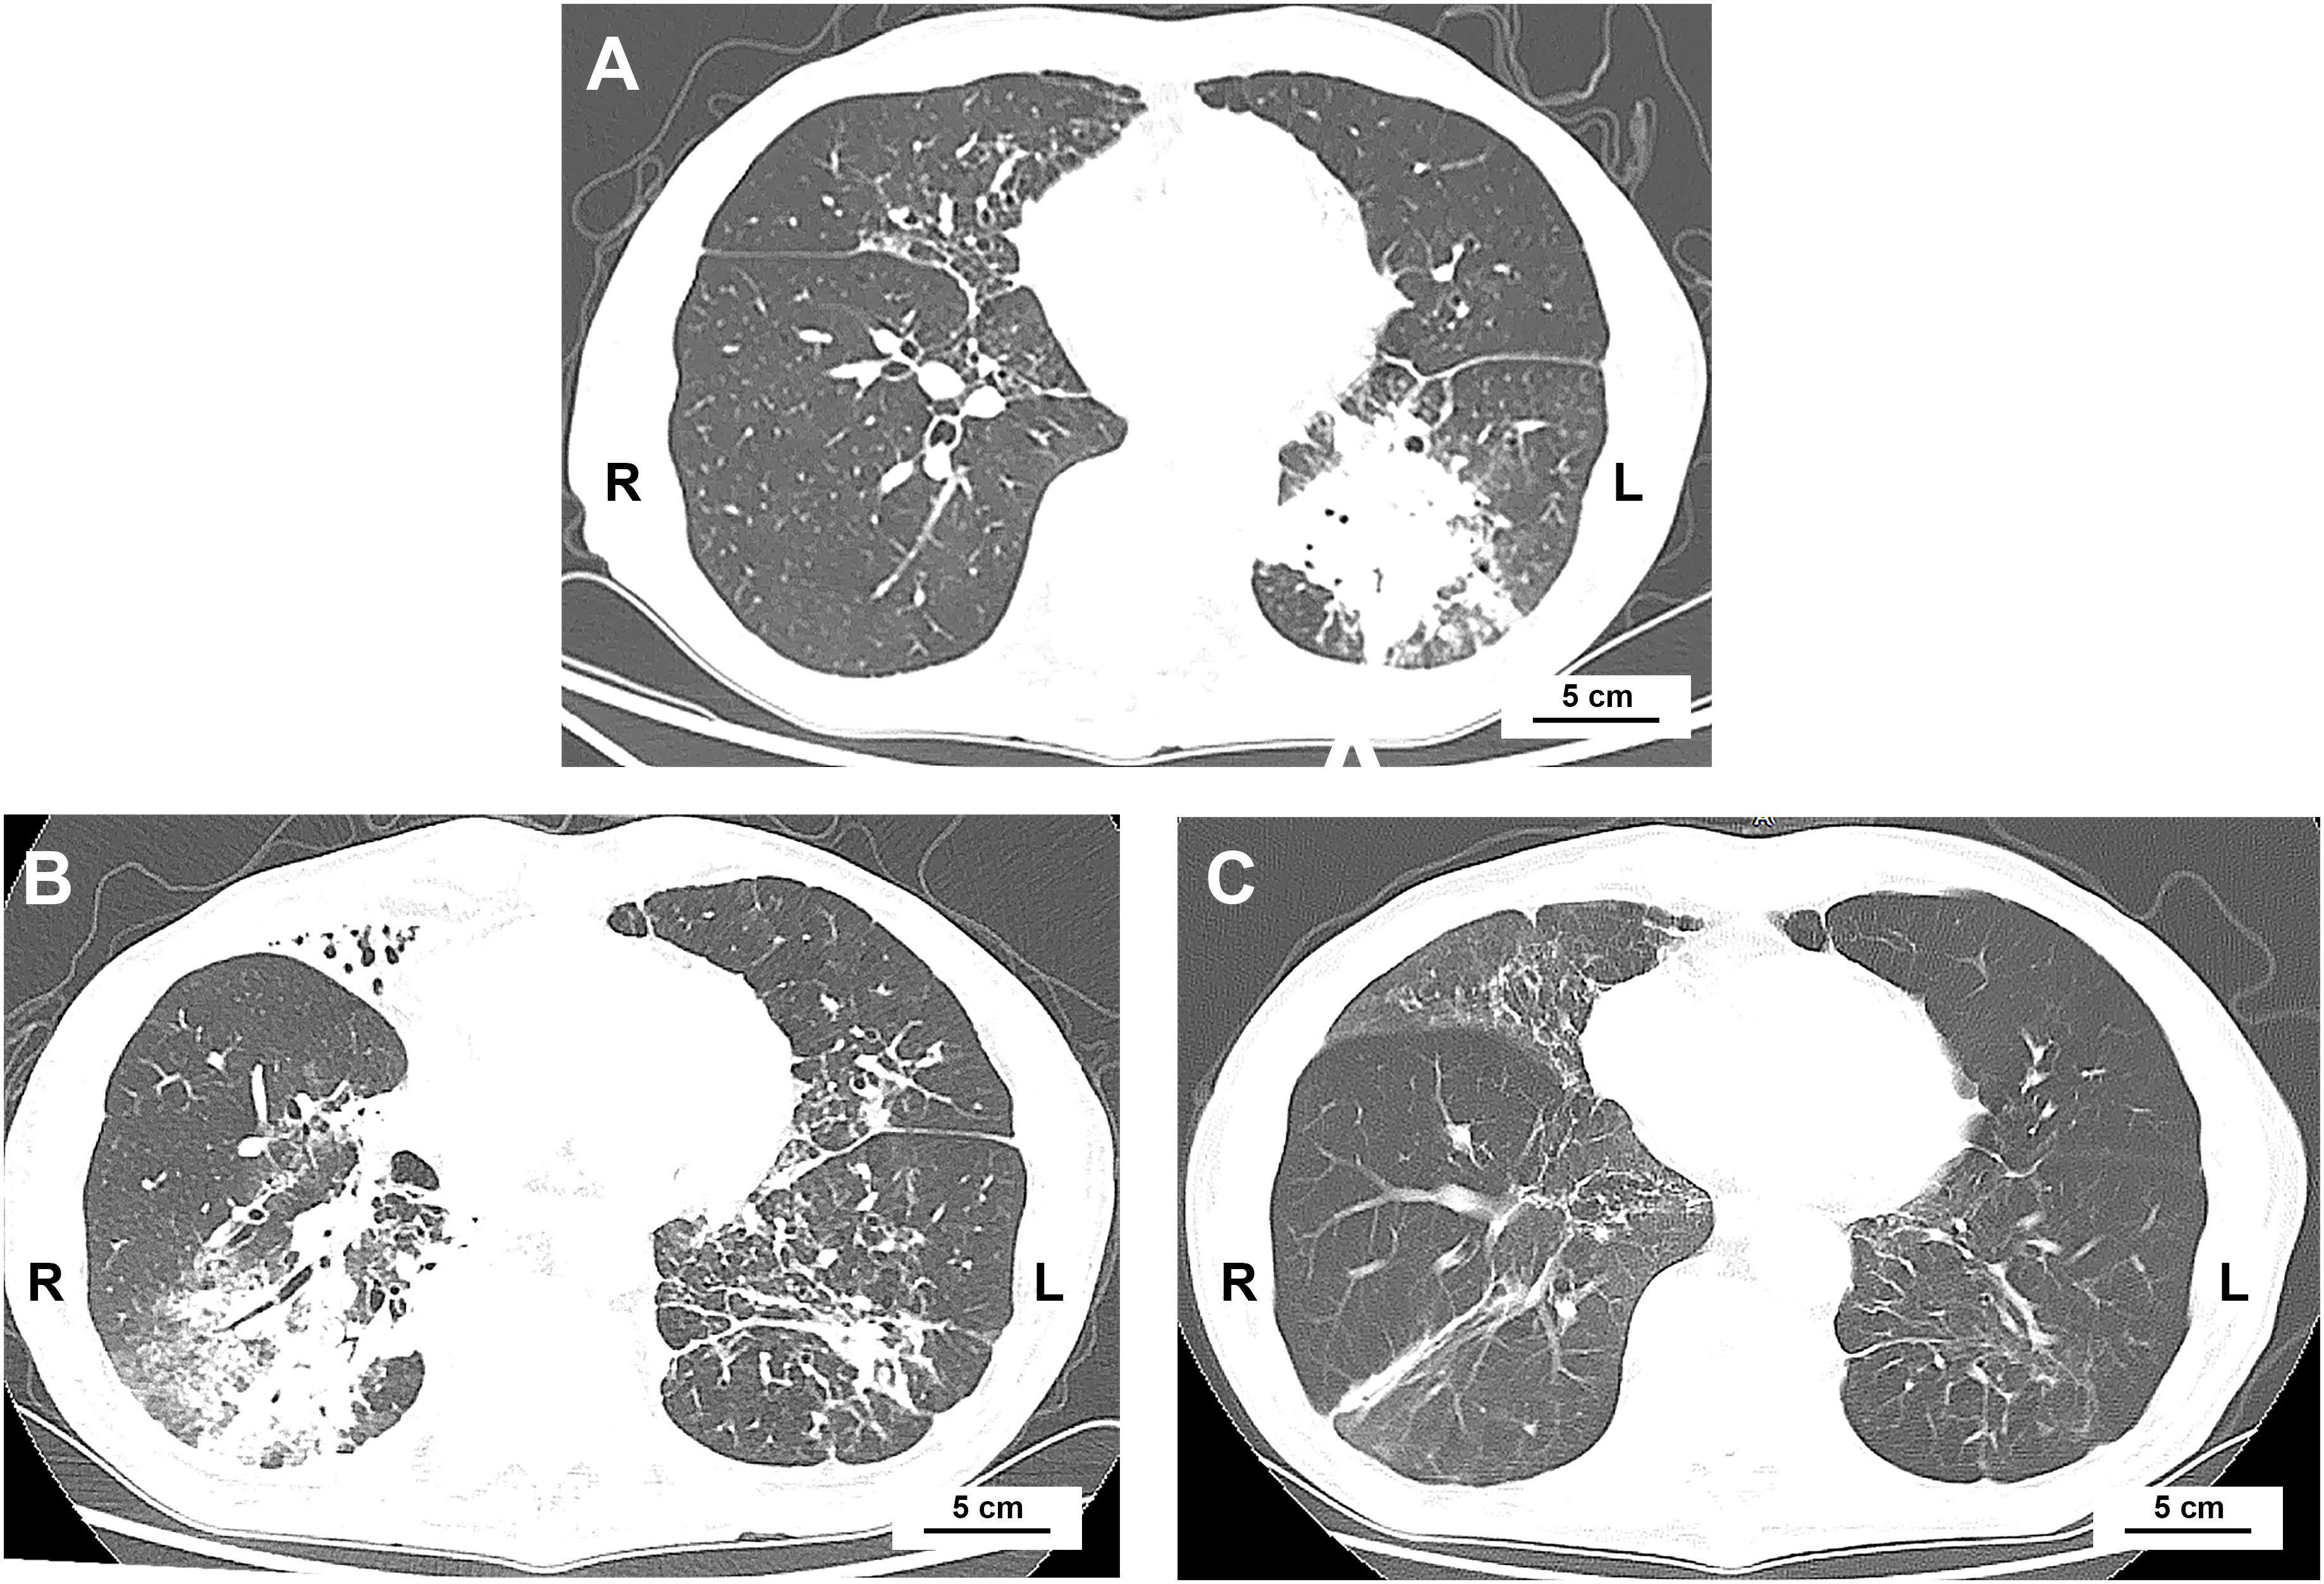

Several immune checkpoint inhibitors (ICIs) have improved outcomes in extensive-stage small cell lung cancer (ES-SCLC), but immune-related adverse events (irAEs) remain a concern. Beyond irAEs, ICIs may induce various immune changes requiring further investigation. A 74-year-old man with ES-SCLC received atezolizumab plus chemotherapy and developed aspiration pneumonia due to dysphagia. Concurrently, elevated anti-glomerular basement membrane, antinuclear, double-stranded DNA, myeloperoxidase-antineutrophil cytoplasmic, proteinase 3 antibodies were detected without any clinical involvement. Moderate glucocorticoids were administered, and during a 3-month follow-up, he remained entirely asymptomatic, with persistently high antibody titers. The case report presents specific autoantibodies following PD-L1 blockage and questions their pathogenic potential.